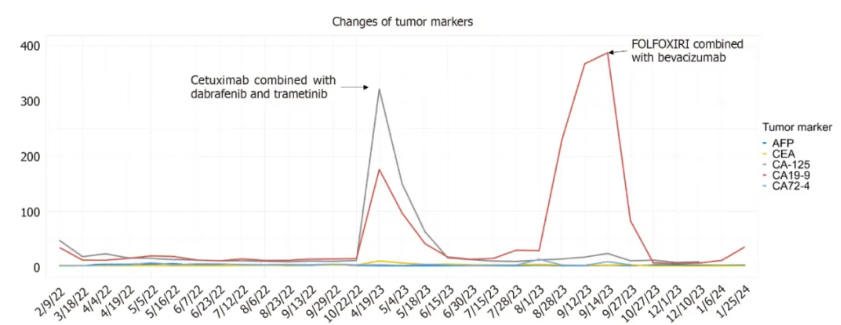

入院时患者肿瘤标志物糖类抗原-125(CA-125)略高(46.8 U/L),随着病情进展和治疗方案的实施,CA-125和CA19-9水平出现波动,而其余肿瘤标志物在整个过程中均保持较低水平(图2)。

图2. 患者肿瘤标志物指标变化

经过达拉非尼、曲美替尼联合西妥昔单抗治疗后,患者血清肿瘤标志物水平逐渐下降至正常范围内,所有转移病灶均出现不同程度的缩小。值得注意的是,阴茎基部的转移病灶尺寸显著减小,从原来的1.6 cm × 1.9 cm缩小至仅0.5 cm × 0.3 cm。同时,相关症状,包括排尿困难和勃起时阴茎疼痛,也逐渐减轻。然而,五个月后,患者病情再次进展,肿瘤标志物(CA19-9)显著升高至388 U/mL。随后,再次调整了FOLFOXIRI联合贝伐珠单抗的治疗方案。不幸的是,患者此后失访。